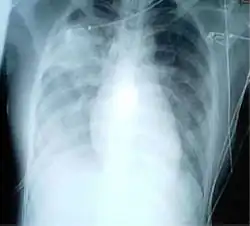

Das schwere akute Atemwegssyndrom, auch Schweres Akutes Respiratorisches Syndrom (englisch severe acute respiratory syndrome, SARS) genannt, ist eine Schwere Akute Atemwegsinfektion (SARI), die erstmals im November 2002 in der südchinesischen Provinz Guangdong beobachtet wurde.[1] Laut dem Bernhard-Nocht-Institut für Tropenmedizin in Hamburg entspricht das klinische Bild einer atypischen Lungenentzündung (Pneumonie). Der Erreger von SARS war ein bis dahin unbekanntes Coronavirus, das man inzwischen als „SARS-Coronavirus“ (SARS-CoV-1) bezeichnet. Die SARS-Pandemie 2002/2003 forderte knapp 800 Todesopfer.[2]

- Entzündung beider Lungenflügel

Rund 25 % der SARS-Patienten, welche an einem Militärkrankenhaus in Peking nach Entlassung betreut wurden, zeigten verbleibende Lungenstrukturveränderung im Sinne einer Lungenfibrose. 40 Patienten hatten eine messbare Diffusionskapazitätsstörung der Lunge. Diese besserte sich spontan bei der Hälfte der Betroffenen. Auch die radiologisch dargestellte Lungenfibrose zeigte im einjährigen Nachbehandlungszeitraum eine Besserungstendenz, verschwand aber nicht bei allen Patienten vollständig. Die Autoren stellten die Hypothese auf, dass aufgrund der Besserung ein anderer Mechanismus als bei gewöhnlichen Lungenfibrosen bestünde. In derselben Studie zeigten sich IgG-Antikörper gegen das Virus bei rund 80 % der Patienten. Aufgrund der Veränderung der Antikörpertiter im Verlauf gehen die Autoren nur von einer zeitlich begrenzten Immunität aus.[10]

Im Rahmen einer sehr kleinen Langzeit-Studie wurden infizierte Mitarbeiter des Gesundheitswesens als SARS-Patienten über 15 Jahre beobachtet. Dabei zeigte sich eine Besserung der Lungenschädigung der Patienten, welche bei Abheilung radiologisch nachweisbare Residuen der Erkrankung hatten. Nach einem Jahr stellte sich jedoch eine Plateauphase mit milden restriktiven Störungen und Diffusionsstörungen ein. Die in den früheren Nachbehandlungsuntersuchungen beobachtete Femurkopfnekrose wurde als Spätfolge der Steroidtherapie im Rahmen der Behandlung des SARS gesehen.[11]